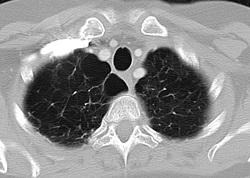

Johns Hopkins researchers say they have identified a new disease gene that, when mutated, appears to increase the risk in a small number of people of developing emphysema and a lung-scarring condition known as pulmonary fibrosis.

Telomere defects that lead to abnormally short telomeres are associated with a condition known as short telomere syndrome that manifests as pulmonary fibrosis-emphysema in adults. Patients are also at risk for bone marrow failure, leukemia and liver disease.

The Johns Hopkins team works with one of the world's largest groups of patients with telomere defects. Started in 2005, the study includes more than 100 families, with individuals ranging in age from infancy to adulthood. Telomere shortening may increase the risk of lung disease in these patients by preventing stem cells from dividing and replacing injured cells in the lungs, making it more difficult for lung cells to replenish themselves when they are threatened by environmental toxins such as cigarette smoke. "This study suggests that telomere defects may be more common than expected in patients with pulmonary fibrosis-emphysema, and it sheds further light on the root cause of these devastating conditions with the hope of identifying new therapies," Armanios says.